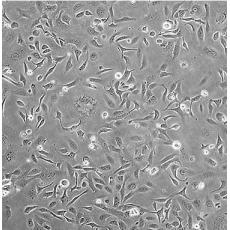

產(chǎn)品名稱 SK-OV-3 [SKOV3]

中文名稱 人卵巢癌細(xì)胞

組織來源 卵巢漿液性囊腺癌;腹水轉(zhuǎn)移;女性

生長(zhǎng)特性 adherent

形態(tài)特征 epithelial

細(xì)胞描述 SK-OV-3 cells are resistant to tumor necrosis factor and to several cytotoxic drugs including diphtheria toxin, cis-platinum and adriamycin.